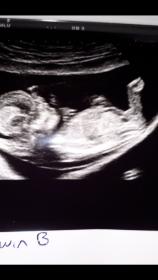

So I had my scan today and confirmed twins, no nub pic from baby A but didn't see anything that screamed boy to me but this is, what I think is a nub, from baby b, am I right in thinking this is likely to be a boy? Thanks.

I don't see any clear gender clues in your pic- that cute little leg is covering the nub area.

The pic is quite small but I zoomed in and I think what I see is nub, not sure as it's not clear. It looks maybe girly but I'm not confident. I do get girly vibes overall though. Hope I'm right!

Not sure if this pic is any better :-)

Slight girl lean but that little leg is in the way.

The angled thing is not a nub. I am giving a ~slight~ pink lean but honestly on my tablet here that is about the size of a stamp so please put no stock into that. Beautiful baby!!!

For me it's really 50:50. I think a part of the nub might be cut off or it's rather short and I see something above the flat line of the nub, which could be stacking or could be a part of the leg as well. So I really don't know in which direction I should lean. Good luck! :-)